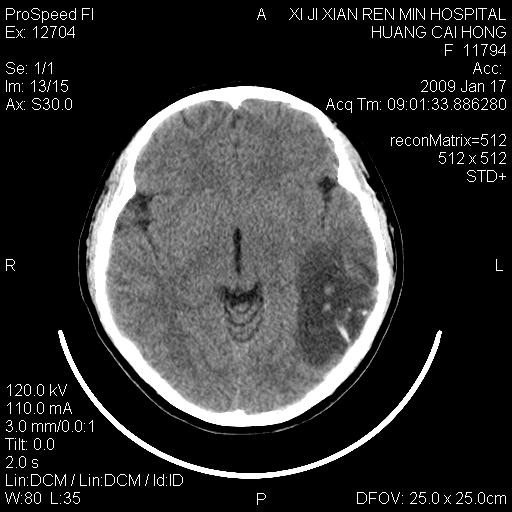

以下是引用zbp537在2009-1-19 13:54:00的发言:[br]首先考虑脑炎。[br]诊断依据:[br]1、患者较年轻。[br]2、有感冒病史。[br]3、左侧颞枕叶这么大一片低密度影,占位征象却不明显,不符合肿瘤特征,其内的高密度影为出血灶。

以下是引用xiaoniu在2009-1-19 13:29:00的发言:[br]左侧颞叶三角形低密度影,占位效应不明显,其内点片样高密都影,青少年患者,首先考虑:少突胶质瘤。因为有感冒病史,不能除外感染的可能。